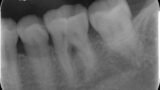

骨がない部分があるのが分かります

まず最初に気になったのは、歯が全体的にすり減っていることです。4000年前のエジプトの人々も、現代のように歯ぎしりをしていたのでしょうか。しかし、それ以上に気になるのは、歯の周辺の骨がなくなっていることです。なぜ他の歯は問題がないのに、この歯だけ骨がないのでしょうか。

展示されていたエジプトの頭蓋骨の歯の状態を見ると、歯周病と根尖性歯周炎が同時に起きていたのではないかと推測されます。どちらか一方の状態から、もう一方の状態へと進行していった可能性もあります。特に奥歯は根っこの形が複雑で、炎症が急速に広がることがあります。

奥歯の分岐部に病気が広がった状態を根分岐部病変と言います。大英博物館での写真がとても分かりやすいです。